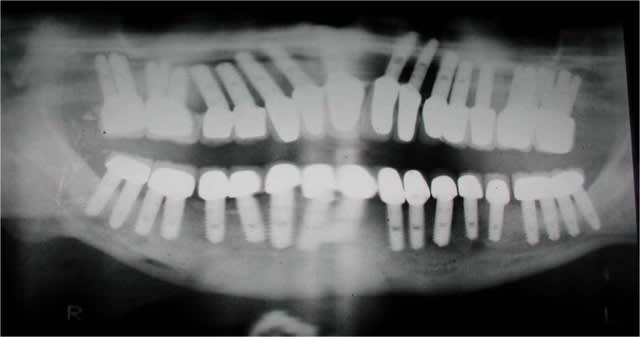

photo2:pano

c'est ne impression photo, je suis au niveau 45-46 juste en distal site ext 45...

je poste la pano et le reste cette sem, j'ai oublié le tout au cab

il est toujours facile de critiquer...mais il me semble que la pose de tes implants est un peu dyssymétrique à savoir que ton dernier implant droit sort en 44....extension risque d'être longue. il faut que ton extension arrive au moins à la première molaire de ton complet sup...pour ne pas le déstabiliser..

peut être vois-je mal..mais c'est l'impression que me donnes les photos.

photo 4:pose de 6 implants evl compacts 4/12 (serf). Tous à plus de 45N, sauf en 36...